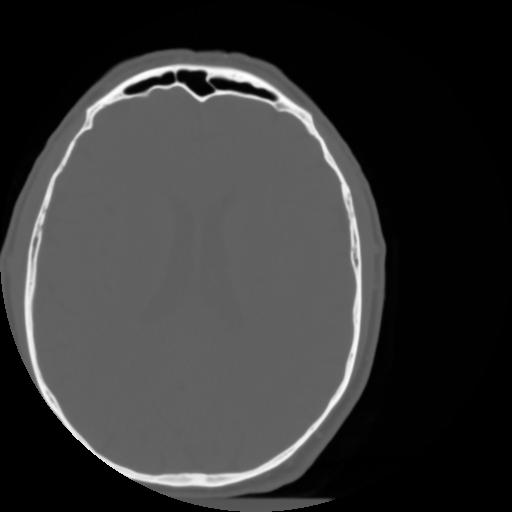

3 CEREBRO,,Axial,3.0,CEREBRO,,